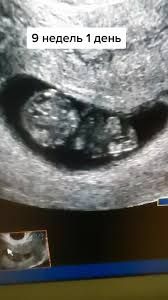

Дарина в Зачатие год Покидайте фото узи в 9 недель 🙏🏻 УЗИ Девочки у кого остались или есть фоточки покидайте пожалуйста! Хочу сходить в 9 неделек на узи, с монитором, хочется узнать как что там примерно видно будет Посмотрите еще 20 записей на эту тему Лучший ответ Елена 9н 2д двойня 02.11.2024 Ответить Отменить Ответить Таня Орозова 01.11.2024 Ответить Екатерина 01.11.2024 Ответить Екатерина Екатерина, чуть больше, 9,5 01.11.2024 Ответить Евгения 9+3 недели 01.11.2024 Ответить ЛисАлис 01.11.2024 Ответить Екатерина 01.11.2024 Ответить Екатерина Екатерина, 9 недель ровно, первое УЗИ 01.11.2024 Ответить Екатерина Екатерина, ножки попка к верху 😄 01.11.2024 Ответить Дарья 01.11.2024 Ответить Евгения Дарья , а вам делали трансвагинально или абдоминально? 01.11.2024 Ответить Дарья Евгения, трансвагинально . А вот 10 недель узи) 01.11.2024 Ответить Евгения Дарья , ух ты) а мне абдоминально делали😁 как в этот раз будут не знаю, пойду в другое место 01.11.2024 Ответить Евгения 01.11.2024 Ответить Мира В интернете нашла)) 01.11.2024 Ответить Девочки подскажите !! Пост нытья Чаты Беременных Выберите чат: Январята-2026 Февралята-2026 Мартята-2026 Апрелята-2026 Майчата-2026 Июнята-2026 Июлята-2026 Августята-2026